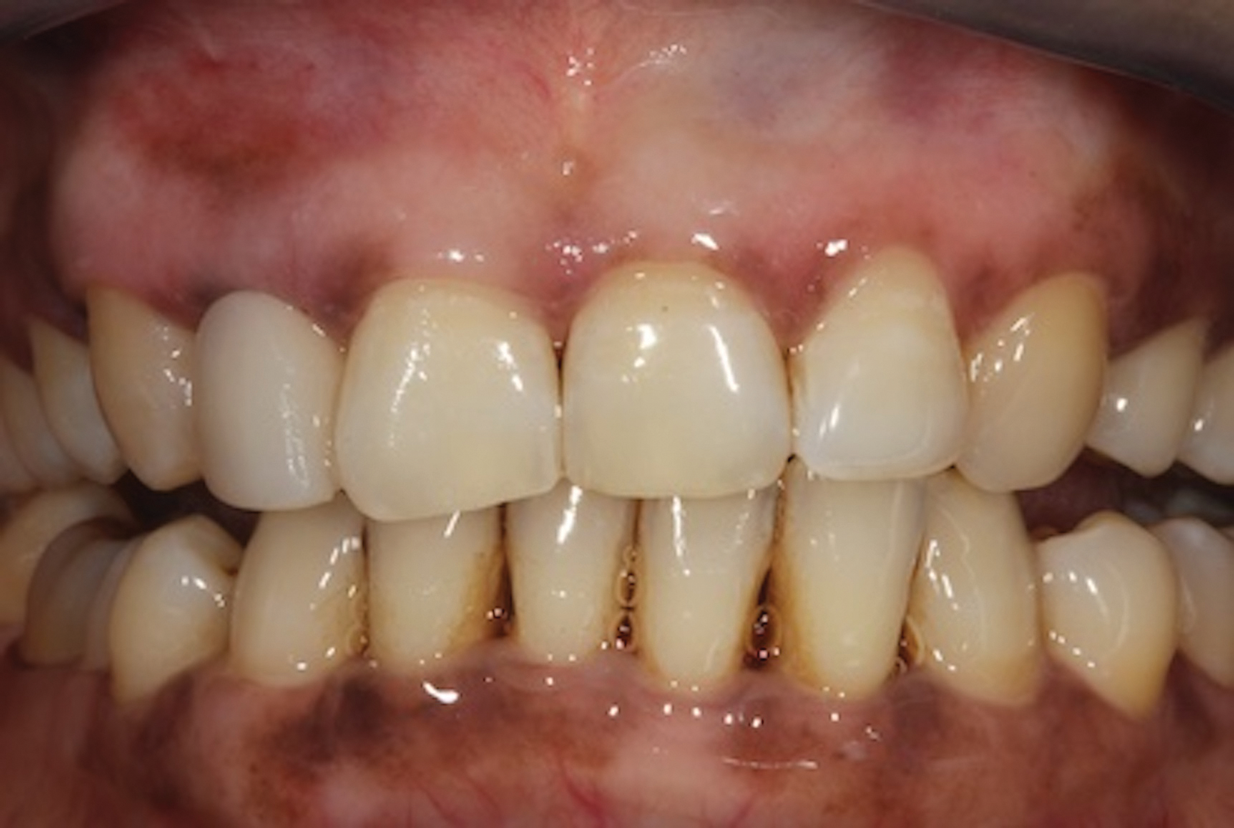

(2.) Close-up right lateral view of the tooth No. 7 site following extraction and implant placement.

Figure 2